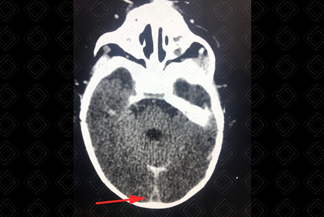

Texto alternativo para a imagem Figura 1. Créditos: Dra. Elazir Mota - Rio de Janeiro/RJ

Descrição das figuras 1 e 2: Tomografia computadorizada do crânio após a administração do contraste venoso. Sinal do delta vazio (seta vermelha): caracteriza-se pela falha de enchimento no interior do seio sagital superior, pela trombose.

• Tomografia computadorizada do crânio: Um dos grandes exames é angiotomografia venosa do crânio, que irá fazer adequado estudo dos seios venosos e das veias corticais. Permite ainda excelentes reconstruções tridimensionais (figura 1). Trombo no interior dos seios venosos, sinal do delta vazio (o sinal é caracterizado por uma área triangular central, que não realça - trombo propriamente dito, delimitada pela dura-máter captante do meio de contraste), congestão venosa e hemorragia subaracnoide. Na tomografia, o infarto ou edema cortical pode ser difícil visualização em fase mais precoce (aguda);